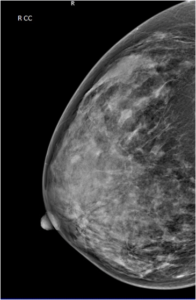

43 year female patient has come for routine screening mammogram.